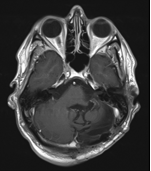

Ladies and Gentlemen, I present my MRI images!

I have to say, I knew it was an unusual request from the start, however a huge thanks to my medical team at The Christie Hospital for providing me with these images and continuing to be awesome.